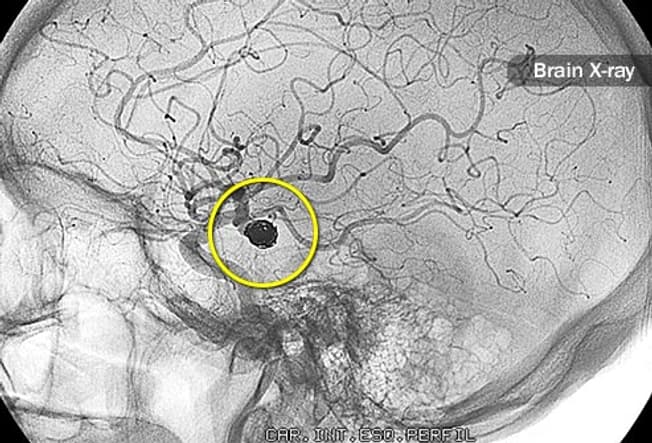

Cerebrovascular Diseases

Your brain needs a constant supply of oxygen-rich blood to work. Without it, brain cells die. Cerebrovascular diseases limit your brain’s blood supply. They include stroke, narrowed blood vessels, aneurysms (weakened arteries), and abnormal clusters of blood vessels called vascular malformations.